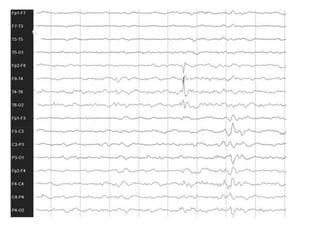

2. Case studies are presented with clinical histories and EEG findings to illustrate different pathologies. Treatment options are also mentioned for many of the conditions.

3. International standards for EEG electrode placement and recording parameters are reviewed. Characteristics of different EEG waves, amplitudes, and patterns are described.